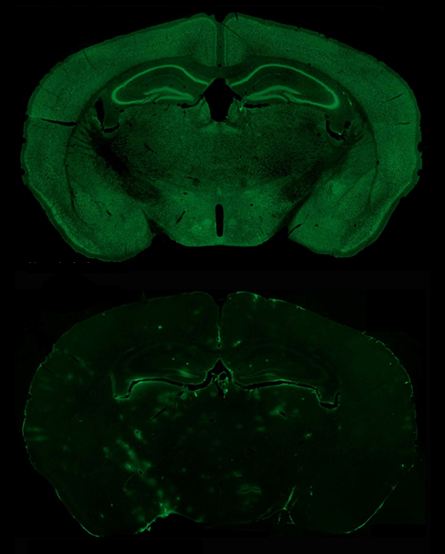

For the new study, University of North Carolina neuroscientist Benjamin Philpot and his colleagues used brain cells from mice genetically engineered so their cells make a fluorescent protein whenever the father’s copy of UBE3A is active. The researchers tested more than 2,000 chemicals to see whether any could turn on the dad’s copy of the gene.